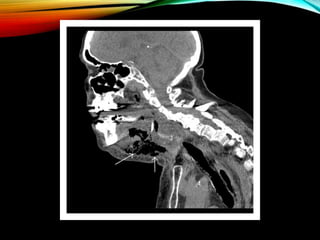

• Cervical soft tissue plain films + CT scan

• CT more useful than standard radiographs

• Lateral soft tissue radiographs useful

• widening of retropharyngeal space

• >3-6mm adults >14mm children (2nd vertebra)

• Presence of gas in prevertebral soft tissue

• Loss of normal lordtic curvature of cervical spine

• CT- inferior extent + plain films